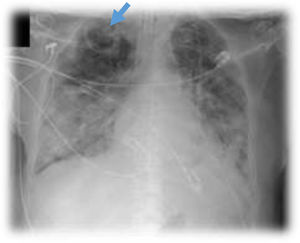

This is the case of a 76-year-old man with a past medical history of anticoagulated AF and mitral prolapse who presents to the hospital with clinical signs consistent with SARS-CoV-2-related pulmonary infection. The patient is diagnosed with bilateral pneumonia with atypical interstitial pattern suggestive of COVID-19 disease.

The patient presented a torpid evolution at the hospital conventional ward with respiratory gradient impairment and need for invasive respiratory support. As part of the medical therapy and with very established selection criteria, interstitial pneumonia with severe respiratory failure was found. The patient was treated with immunosuppressants, tocilizumab, and steroids. The patient showed a bronchial aspirate of Aspergillus fumigatus. The images reveal the presence of cavitatary lesions (aspergillosis) (Figs. 1–3).